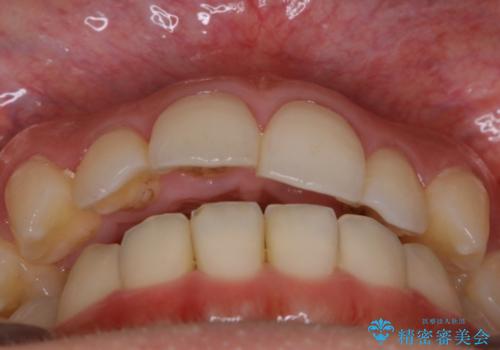

- 歯のガタつきによる見栄えや清掃困難を主訴にご来院されました。

左側の噛み合わせは上の歯が前方に寄ってきてしまっていることが原因のズレがありました。

歯列弓の拡大

歯並びが悪くなる原因の一つに「歯列弓の狭窄」というものがあります。

奥歯や前歯が内側(舌側)に倒れ込んでしまったり、歯が生えてくる位置が内側になってしまうことにより歯並びのアーチが狭くなってしまうことを言います。

このような場合、歯並びのアーチを拡大してあげるだけでもガタつきを無くすためのスペースがかなり作れることがあります。